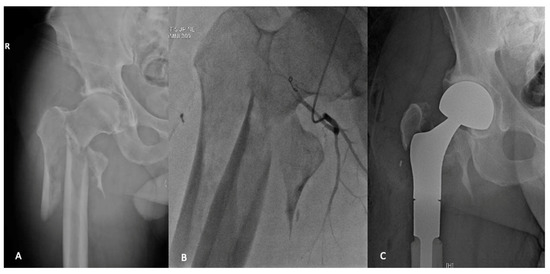

7.2. Endoprostheses

- Chatziioannou, A.N.; Johnson, M.E.; Pneumaticos, S.G.; Lawrence, D.D.; Carrasco, C.H. Preoperative embolization of bone metastases from renal cell carcinoma. Eur. Radiol. 2000, 10, 593–596. [Google Scholar] [CrossRef]

- Geraets, S.E.W.; Bos, P.K.; van der Stok, J. Preoperative embolization in surgical treatment of long bone metastasis: A systematic literature review. EFORT Open Rev. 2020, 5, 17–25. [Google Scholar] [CrossRef]